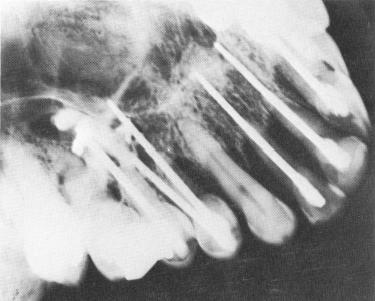

Fig. 13-62. Overshooting accidents. A, The post overshot a lower premolar and went through the jaw. It was immediately withdrawn into the bone and this radiograph taken. B, Five weeks later. C, In this case, overshooting was detected only after cementation. Radiograph taken 1 year after the operation. (From Orlay, H. G.: Endodontic implants, J. Oral Implant Transplant Surg., pp. 44-53, 1965.)

Fig. 13-63. Pins perforating the maxillary sinus. Although usually no problems arise for the patient, the pins become more unstable. (Courtesy H. G. Orlay.)

Fig. 13-64. Pins perforating the nasal vestibulum as well as the sinus. The pin in the nose will be very irritating. (Courtesy H. G. Orlay.)